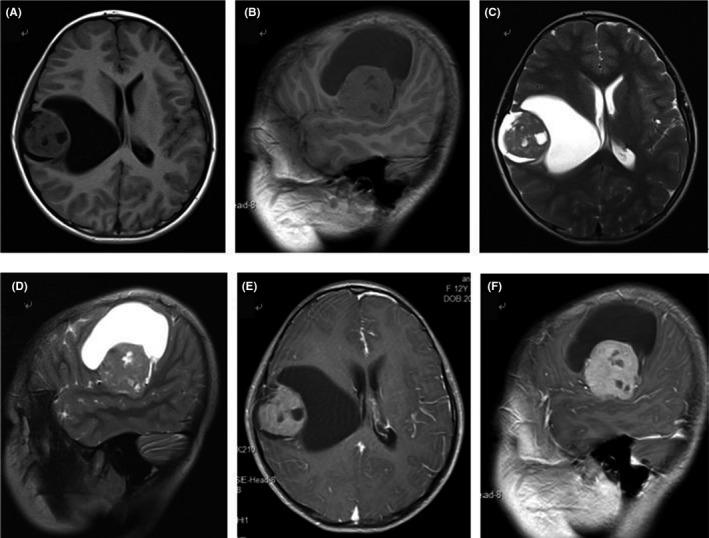

A 13-year-old girl presented with parkinsonism symptoms of clumsiness in her left leg and hand. Her mother was diagnosed with Parkinson's disease at age 30, nine years previously. Magnetic resonance imaging showed a lesion in the temporal lobe with long-T1 signal, mixed-T2 signal. The patient was taken in for a right tumorectomy and was diagnosed as having an ependymoma postoperatively. The patient's symptoms fully resolved in the postoperative phase.

The case describes the mechanism of intracranial ependymoma involving parkinsonism symptoms. Our findings suggest that in some patients presenting with atypical PD symptoms the underlying cause should not be overlooked; MRI examination is necessary.